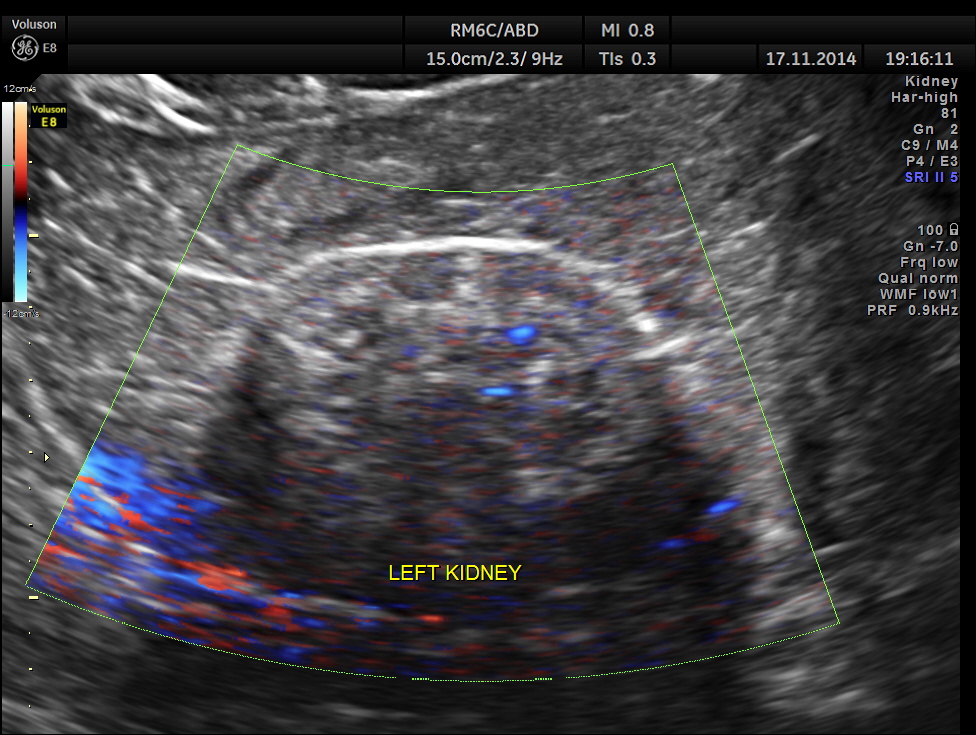

The following pictures show the transplanted kidney in the Right Iliac Fossa, with normal architecture, good Power Doppler flow and normal Spectral Doppler values.